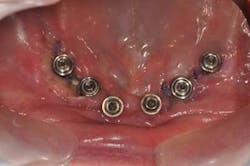

Mandibular arch: the lower jaw is fully edentulous. Initially, according to the patient, an implant-supported five-unit bridge (23 to 27) was made on four implants (Alphabio®) placed in 2007. Tooth 22 was present at the time and a removable partial denture replaced the bilateral posterior missing teeth.

Then, in January 2012, tooth 22 was extracted and a second implant specialist placed a new implant (Zimmer Dental®) to replace it. The GP decided to use a Locator® attachment system on this new implant and have the existing denture stabilized over it, without paying any attention to the collapsing situation of the upper right.Fig. 3: CT scan shows the existing implants positions and the bone volume available